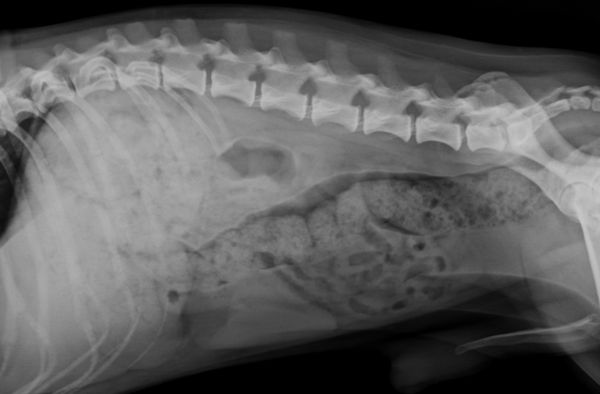

Radiology Support

Need a hand with radiographs, CT, MRI or US loops? We’ve got you covered. Our team provides detailed, high-quality reports to support you in managing your cases.

In addition to interpreting images, we can also provide imaging protocols for specialized CT or MRI studies (for example: urinary tract excretory contrast CT, lymphangiography, etc.). Let us know if you have questions about the imaging in advance.

Over the years, we’ve learned that imaging reaches its full potential when interpreted in context. That’s why for radiographs, CT, MRI, and ultrasound cases, our radiologist can collaborate with clinical specialists who can review the case in depth. After reviewing the images, the specialist can discuss the next steps with you—from further work-up to treatment planning.